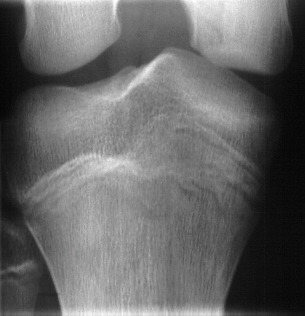

This 16 year old, 220 pound male presented to the emergency

room after sustaining an acute injury to his right knee while

playing baseball. The patient related that he noticed acute onset

of pain in the right knee after striking out at bat. He heard

a single clunk in his knee and noticed immediate pain and swelling.

On examination he was noted to have medial knee tenderness with

a mildly positive apprehension test. His ACL, PCL, MCL and LCL

ligaments were intact. He was placed into a knee immobilizer and

told to follow up in the Sports Medicine clinic. He presented

to Sports Clinic 6 days later with a reporting the knee "gave

out" on him several times since the accident. On physical

exam of the patient, six days after injury the knee was noted

to have a large effusion. ROM was limited from 20 to 100 degrees

of flexion. There was significant medial retinacular tenderness

with a mildly positive apprehension test. Based on the radiographs

and his clinical exam an arthroscopic examination was performed.

At arthroscopy the medial femoral condylar defect was not apparent,

but a large retinacular tear was discovered. Also, the patient

had an osteochondral fracture of the lateral femoral condyle and

a free 7 mm by 5 mm intraarticular cartilage fragment.